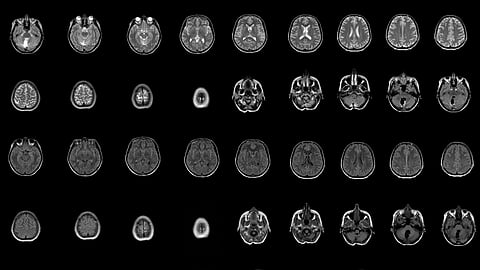

How Brain-Computer Interfaces Could Restore Speech and Help Fight Depression

Already, brain-computer interfaces have helped to control epileptic seizures and decrease tremors in patients with Parkinson's disease. The next wave will tackle even more complex applications, like restoring speech and regulating mood.

Dr. Chang says the aim is to decipher the brain activity that underpins complex human behaviors, like speech and emotions, in an attempt to develop therapies that could help people who can't speak or who suffer from neuropsychiatric conditions like depression and anxiety.

We're really interested in trying to understand what is going on when someone is processing emotions normally, and what the signals look like in people who have depression and don't have normal regulation of their mood. Our hope is that by understanding these electrical signaling patterns that we can use them as biomarkers, as ways to understand when and what parts of the brain are involved when someone is having depressive episodes. And then the second thing, which is far more important, is to use that information to intervene and to regulate some of these areas so that someone feels more normal, like they aren't in incapacitating depression.